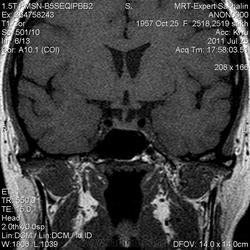

Женщина.6 лет назад выявлено образование левой доли нейрогипофиза.Пришла на контроль.

Постконтраст

Мне самой показался случай не совсем ясным, но динамик четко показывает участок с отставанием в контрастировании, воронка смещена вправо-о чем  думать бедному начинающему специалисту?